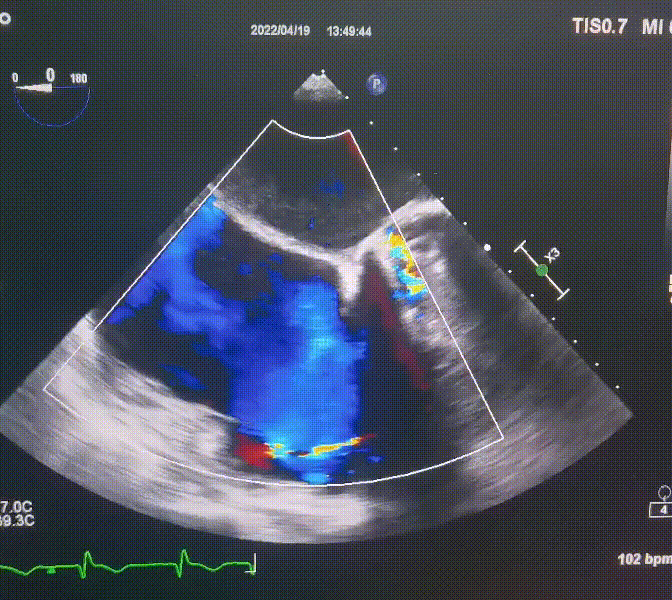

術(shù)前超聲提示:

1.右心、左房明顯增大;

2.二尖瓣人工機(jī)械瓣功能正常,無瓣周漏;

3.三尖瓣環(huán)巨大擴(kuò)張,收縮期瓣葉對(duì)合不攏,收縮期三尖瓣房側(cè)見大量反流信號(hào),反流面積15-20cm²,TRVmax:240cm/s,跨瓣壓差:23 mmHg。

圖1.術(shù)前超聲